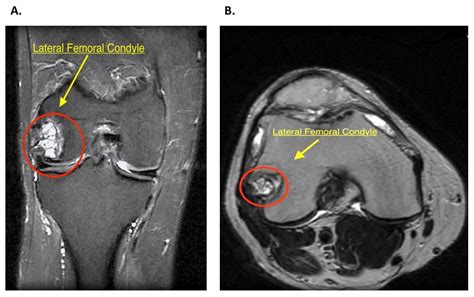

Radiographic Imaging of the Intercondylar Fossa

Because the intercondylar fossa of femur is located on the posterior aspect of the distal femur, it is not always visible on standard anteroposterior (AP) knee X-rays. To properly visualize this structure, medical professionals use a specialized view known as the "notch view" or "tunnel view."

During a notch view, the patient is typically positioned on their hands and knees or standing with the knee partially flexed. This angle allows the X-ray beam to pass directly through the intercondylar fossa of femur, providing a clear projection of the notch space. This imaging technique is vital for detecting:

• Osteochondral defects (damage to the cartilage/bone within the notch).

• Loose bodies (fragments of bone or cartilage floating in the joint).

• Notch stenosis (narrowing caused by bone spurs or osteoarthritis).